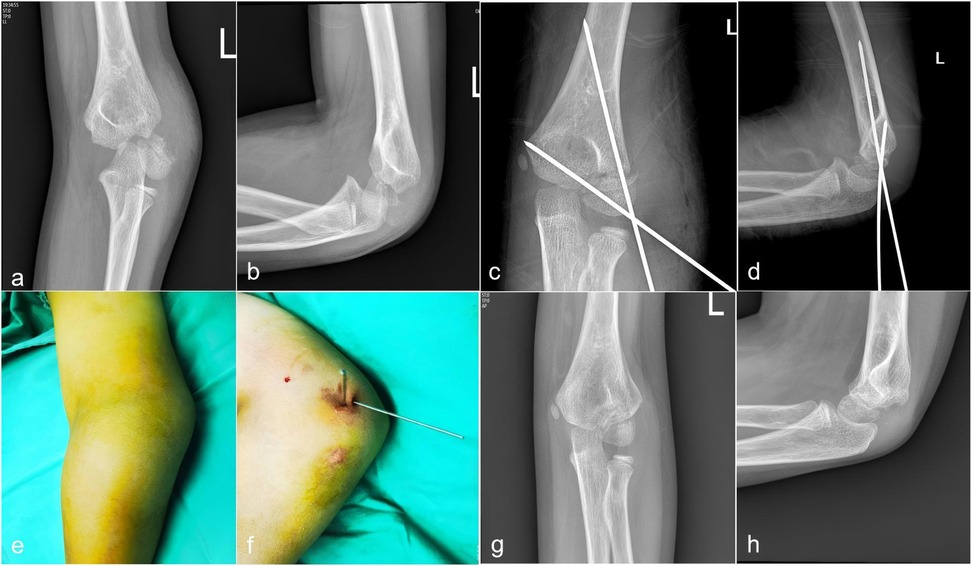

Figure 2 illustrated the sequential imaging and clinical appearance of a representative case of Song V lateral humeral condyle fracture that was successfully treated with closed reduction percutaneous pinning and achieved a final MEPS of 100 points.

Figure 2

Sequential imaging and clinical appearance of a representative case of Song V lateral humeral condyle fracture treated with closed reduction percutaneous pinning. (a,b) Preoperative anteroposterior and lateral radiographs showing complete displacement and rotation of the lateral condylar fragment. (c,d) Intraoperative radiographs after successful closed reduction and Kirschner wire placement. (e,f) Clinical photographs of the elbow following percutaneous pinning, demonstrating minimal surgical wound. (g,h) Follow-up AP radiograph at 12 months postoperatively, showing complete fracture union without evidence of avascular necrosis or significant deformity.